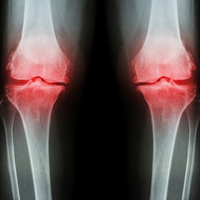

"Multipl Miyelom, lenfomadan sonra ikinci sırada bulunan bir lenf bezi hastalığıdır. Kemiklere hasar verip, ağrılara, kırıklara hatta felce yol açan bu hastalık böbrek yetmezliği ve bağışıklık sistemindeki bozukluklara da sebep olarak vücudu mikroplara karşı savunmasız hale getirmektedir. Kanda yüksek sedimantasyon değeri, kansızlık, kemik ağrıları, enfeksiyon gibi belirtilerle kendini gösteren Multipl Miyelom'un tanısını koymak için, kan ve idrarda bazı özel biyokimyasal araştırmalar yapılması gerekmektedir. Yapılan tetkiklerde Miyelom riski olması durumunda kemiklerin durumunu ve kemik iliğindeki hücrelerinde incelenmesi gerekmektedir"